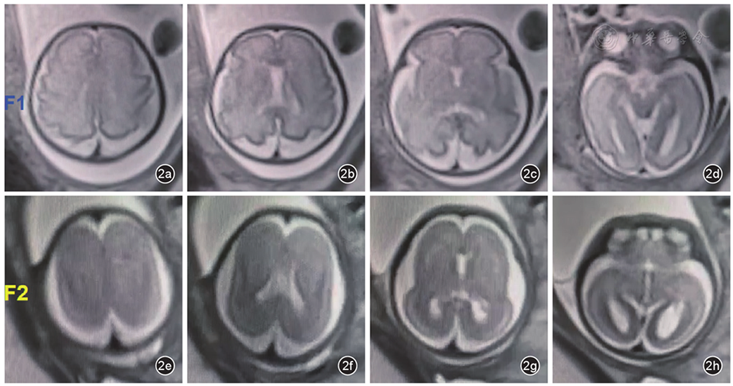

该孕妇孕28周行MRI检查(图2):F1胎儿:颅脑结构未见明显异常;F2胎儿:双侧大脑半球表面脑回脑沟光滑,双侧外侧裂变浅,双侧中央沟、中央前沟、中央后沟、扣带沟、距状沟、顶枕沟未见显示。左侧侧脑室后角宽约10.5 mm。MRI提示:F1胎儿头颅MRI平扫未见异常。F2胎儿双侧大脑皮质发育异常,考虑先天性无脑回-巨脑回畸形;较F1胎儿头围明显小,左侧侧脑室后角轻度增宽。

图2 孕28周双绒毛膜双羊膜囊胎儿颅脑MRI检查图像。图a ~ d为F1胎儿,图e ~ h为F2胎儿。F1胎儿大脑皮层发育指标:顶枕沟形态良好,距状沟开始折叠,中央沟可见,中央前后沟可以识别,扣带沟清晰显示;F2胎儿双侧大脑半球表面脑回脑沟光滑,双侧外侧裂变浅,双侧中央沟、中央前沟、中央后沟、扣带沟、距状沟、顶枕沟未见出现